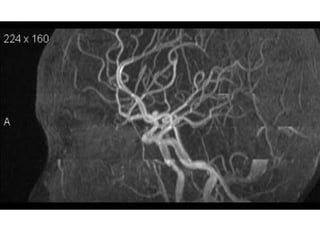

Arteries of the brain (lateral view) - MRA

1. Anterior cerebral artery

2. Anterior communicating artery

3. Basilar artery

4. branches (in insula) of middle cerebral artery

5. Cavernous portion of internal carotid artery

6. Cervical portion of internal carotid artery

7. Genu of middle cerebral artery

8. Intracranial (supraclinoid) internal carotid artery

9. Middle cerebral artery

10. Ophthalmic artery

11. Petrous portion of internal carotid artery

12. Posterior cerebral artery

13. Posterior cerebral artery in ambient cistern

14. posterior cerebral artery in interpeduncular

cistern

15. Posterior communicating artery

16. Posterior inf cerebellar artery.

17. Quadrigeminal portion of posterior cerebral

artery

18. Superior cerebellar artery

19. Vertebral artery